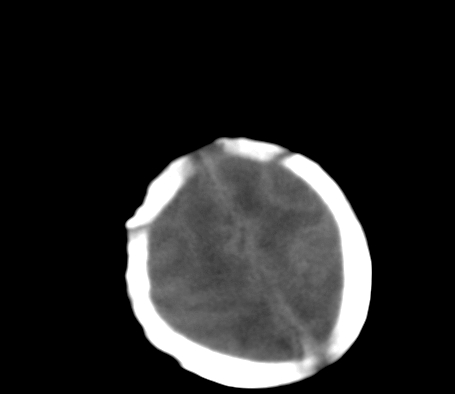

患儿,出生时正常,第5天突然呕吐两次,无发热及抽搐。

片示:双侧大脑半球脑实质密度降低,皮髓分界尚清,左侧顶部脑沟内见铸形高密度影,脑中线结构居中。

2、hie并少量蛛网膜下腔出血。